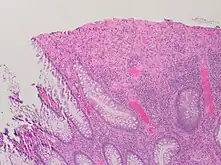

A micrograph demonstrating cryptitis, a microscopic correlate of colitis. H&E stain.

An important investigation in the assessment of colitis is biopsy for histopathology. A very small piece of tissue (usually about 2mm) is removed from the bowel mucosa during endoscopy and examined under the microscope by a histopathologist. A biopsy report generally does not state the diagnosis, but should state any presence of chronic colitis, give an indication of disease activity, as well as state the presence of any epithelial damage (erosions and ulcerations).[4]

Histopathology findings generally associated with chronic colitis include:[4]

Other findings include basal plasmacytosis and mucin depletion.[4] Histopathology findings generally associated with active colitis include:[4]